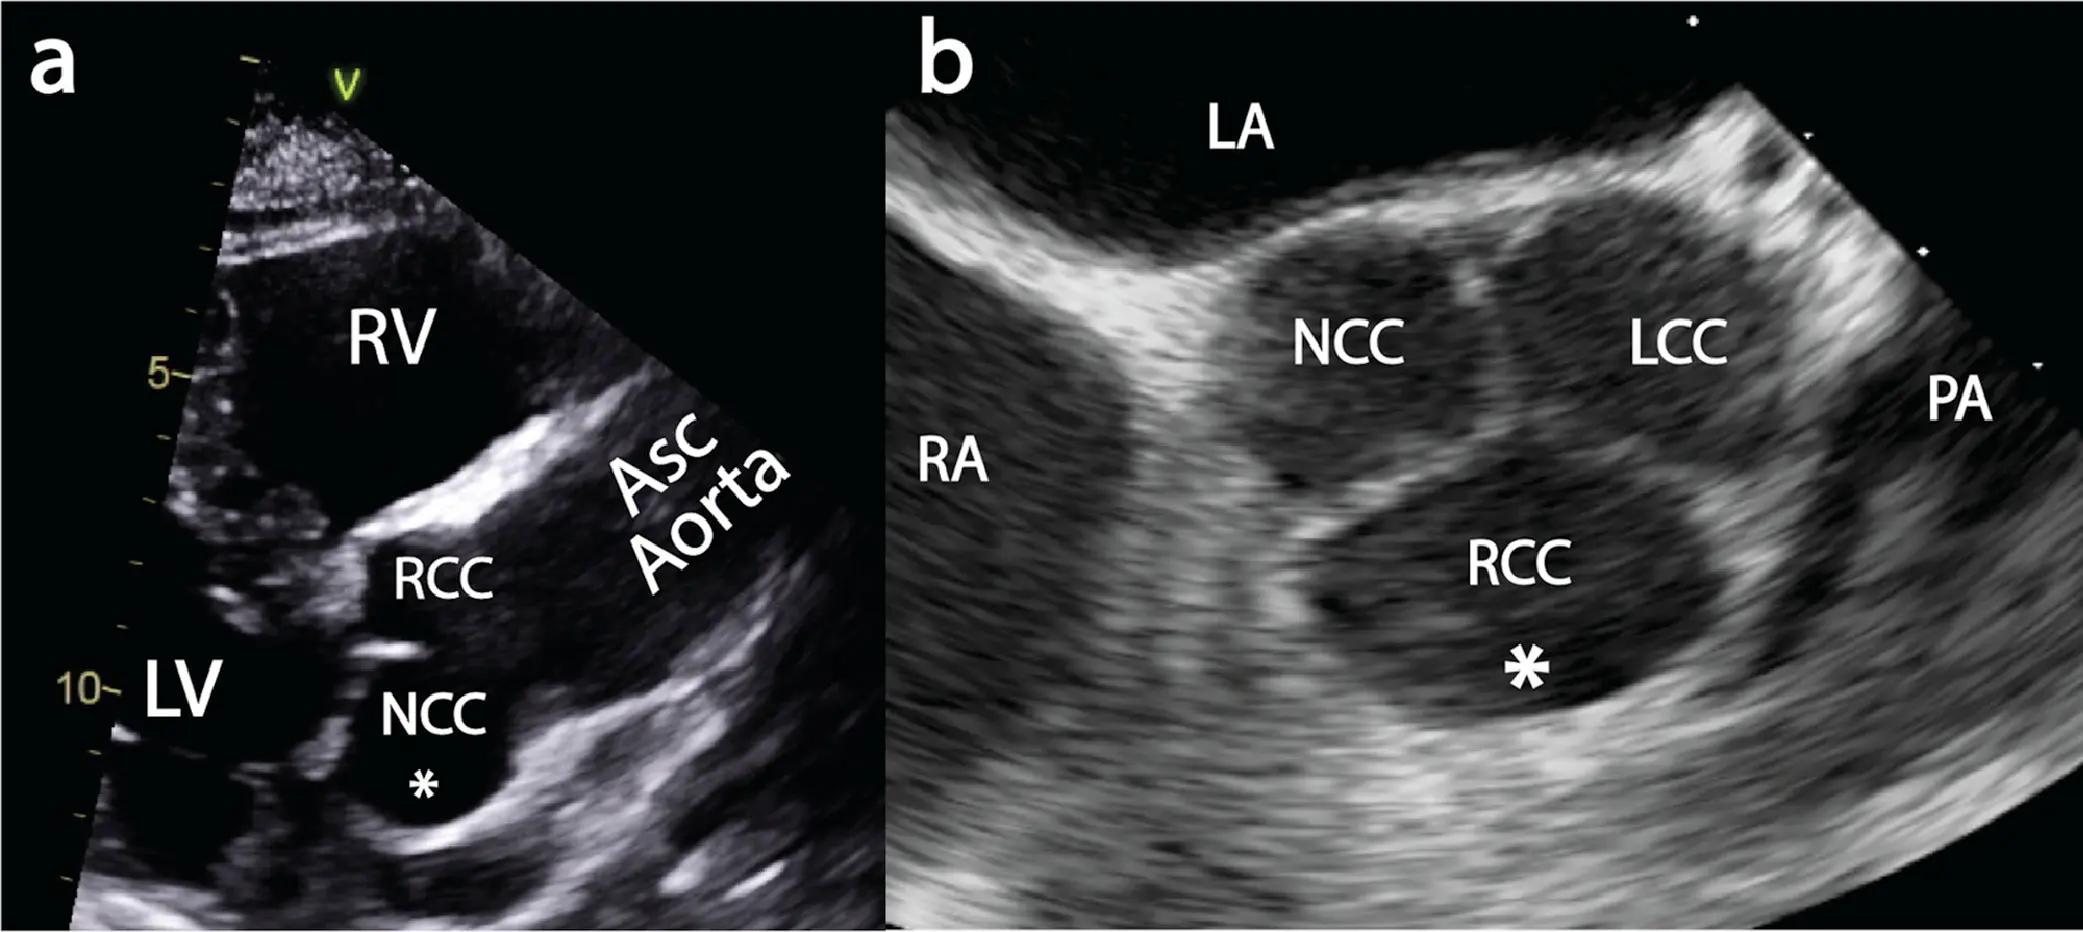

Sinuses of Valsalva

- The aortic root diameter at the sinus of Valsalva is measured in the PLAX view using the leading edge to leading edge method (from the leading edge of the anterior root wall to the leading edge of the posterior aortic root wall) and is measured at end-diastole (end-diastole can be recognized as being at the onset of the QRS).1

- With TEE, aortic measurements are performed from the mid-esophageal (ME) long-axis view at end-diastole, using the leading edge-to-leading edge technique 2